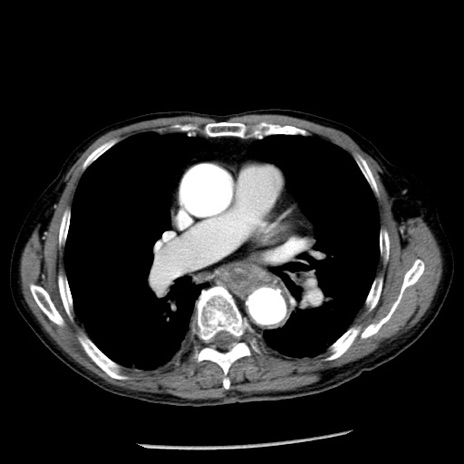

症例26(横断像)

【症例】80歳代男性

【主訴】嘔吐

【現病歴】昨晩2回嘔吐あり、今朝になっても嘔吐あり。来院。

【既往歴】胃潰瘍

【身体所見】意識清明、BT 37.6℃、BP 166/95mmHg、HR 100bpm、SpO2 97%、腹部:平坦・軟、腸蠕動音聴取良好、圧痛なし。

【データ】WBC 21900、CRP 1.46